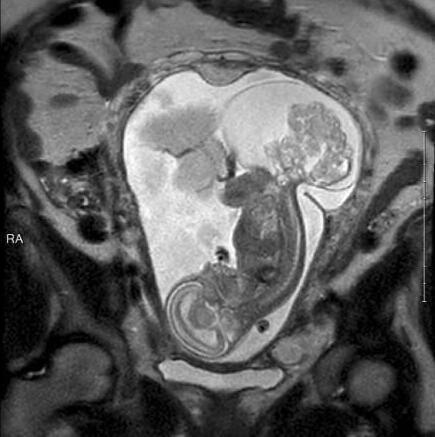

胎儿23周被取出子宫手术后放回 36周健康出生

据CNN报道,美国德克萨斯州的玛格丽特-伯默怀孕16周的时候去做常规产检。不幸的是,产检时医生告诉玛格丽特胎儿患上了一种罕见的肿瘤。“医生告诉我胎儿已经患上了骶尾部畸胎瘤。我当时非常震惊,也非常害怕,因为我们从来没听过这种病,不知道会发生什么。”玛格丽特接受采访时说。